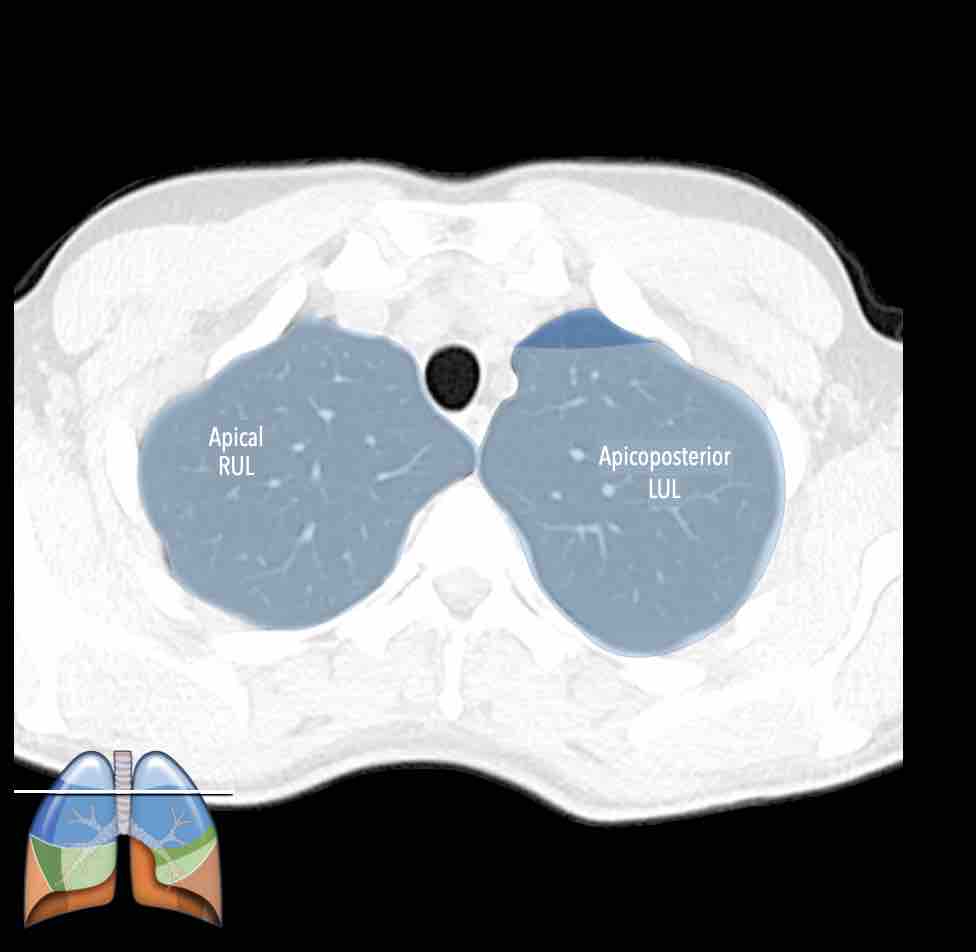

Các phân thùy phổi trên CT

Cuộn qua các hình ảnh để quan sát cách phổi được phân chia thành các phân thùy.